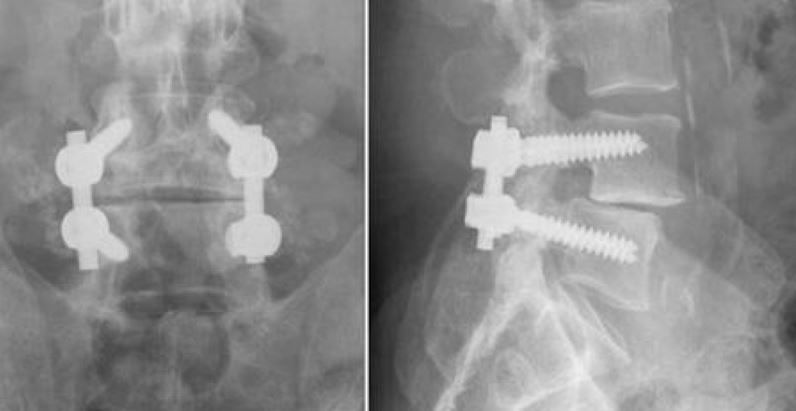

Back and side views of posterolateral fusion with screws.

These X-rays show front and side views of posterolateral lumbar fusion.